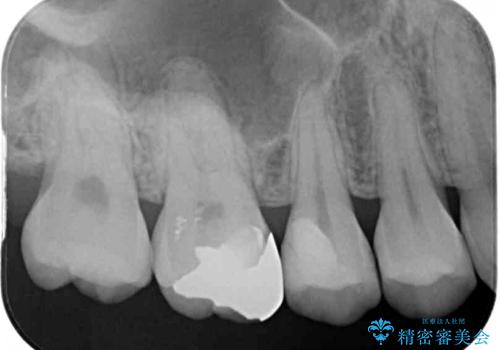

レントゲン写真より、第一小臼歯にやや大きい虫歯があることが分かりました。

症状などから診断したところ、神経を取る可能性は低いと考えられたため、セラミックインレーによる修復治療を行うこととしました。